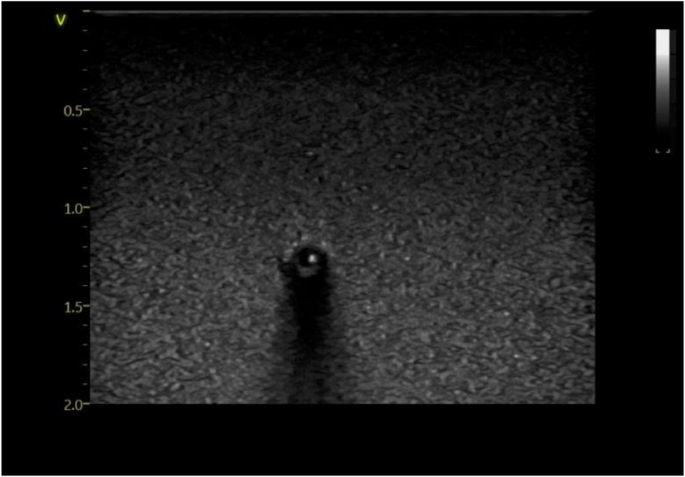

After placing water-based ultrasound jelly on the cannulation phantom, the operator placed a linear array probe (8-18 MHz GE, Vivid S70N, Bedfordshire, UK) held in the non-dominant hand to obtain optimal short axis (cross-sectional, out of plane view) and long axis (longitudinal, in plane) views of the vessel. Using the dominant hand, a 22G needle with a length of 40 mm was inserted at an angle of about 30–45 degrees, at a point 5–10 mm proximal to the middle marker of the probe on to the surface of the phantom, while keeping an optimal cross-sectional view. The needle was inserted until it reached the anterior wall of the vessel. The needle was then cautiously advanced at a shallower angle with ultrasound imaging of the indentation and penetration of the anterior wall of the vessel. The puncture of the vessel was also felt by the operator mimicking what one may expect in clinical practice. Extreme care was taken to ensure that the tip of the needle was maintained in the middle of the vessel lumen giving the appearance of a bullseye while gradually advancing the needle and the probe in short < 1 mm increments. This was to ensure that the needle did not breach the posterior vessel wall and the entire length of the needle tip was inserted. Once the needle was confirmed to be in the centre of the vessel lumen using US, a metal guidewire was inserted through the needle for insertion of a PICC using a Seldinger technique (Figs. 3 and 4). A metal guidewire was used as it could easily go through the caliber of the needle that was used and could readily be visualized using US. Non-ultrasound confirmation of the correct placement was also achieved by continued advancement of the guide wire which resulted in the guide wire being physically visible at the exit end of the vessel outside the phantom.

Ultrasound illustrating the characteristic bullseye sign with the guide wire seen as an echogenic dot within the vessel lumen.